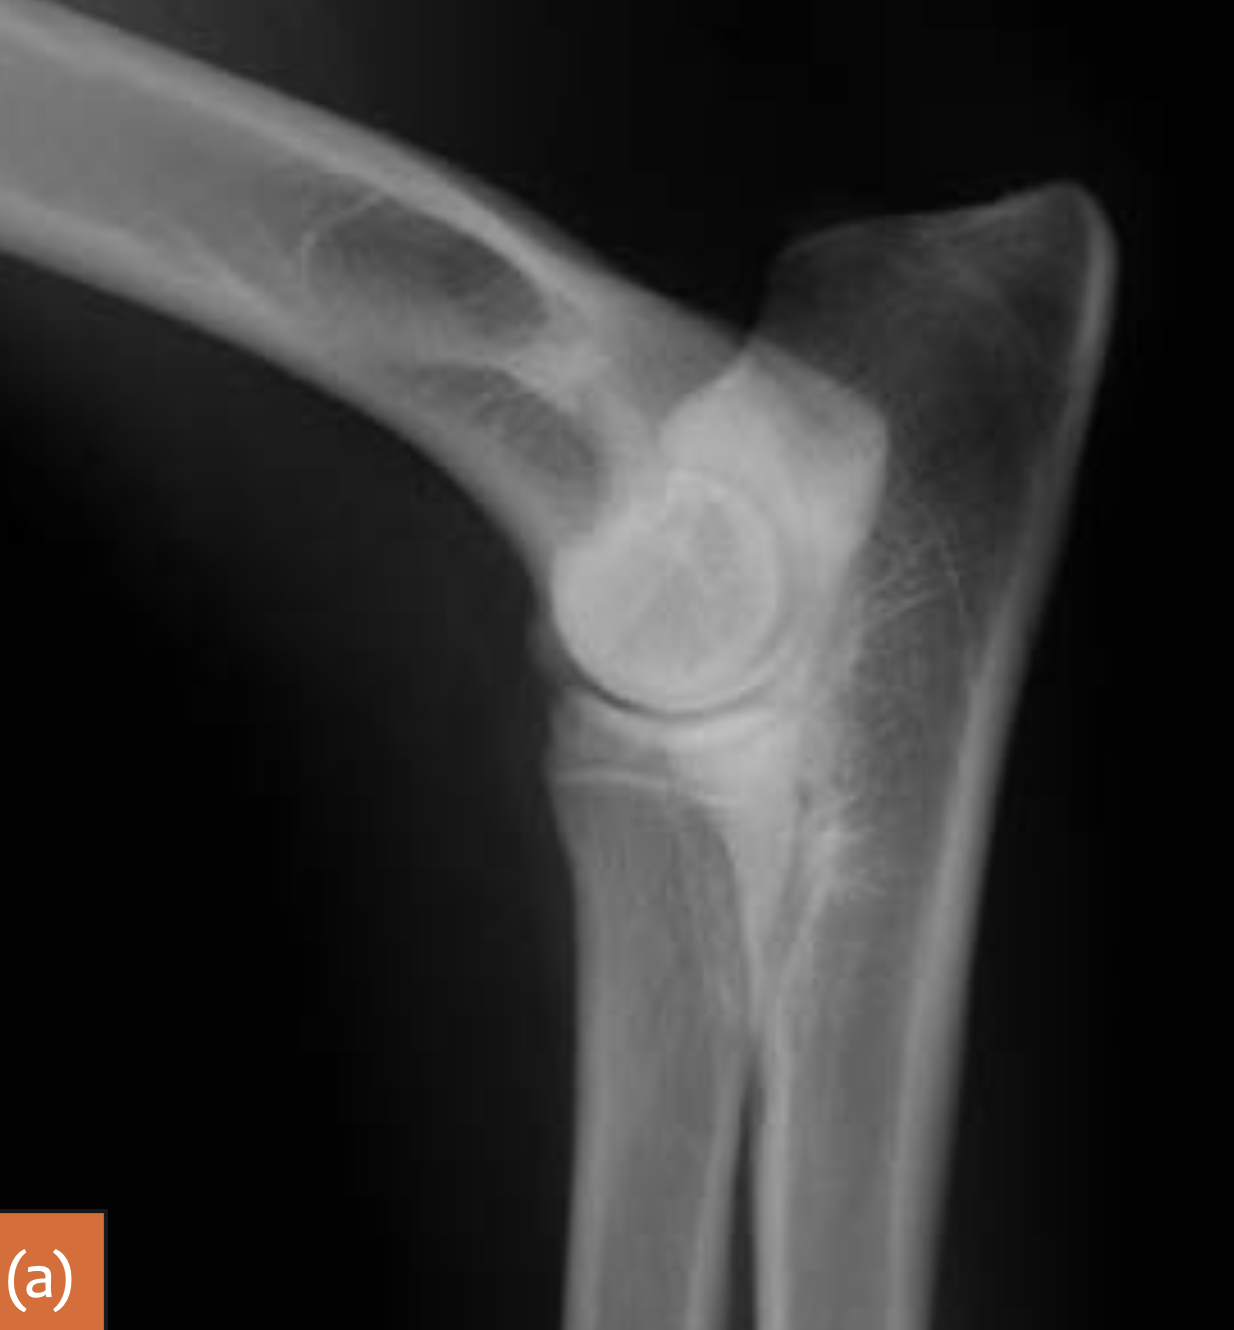

5m JRT

Congenital proximal radial luxation or subluxation usually occurs in larger breeds such as Shetland Sheepdogs and Bulldogs. Clinically, there may be only mild deformity or lameness. The radius usually luxates caudolaterally. The radial head is often underdeveloped and rounded.